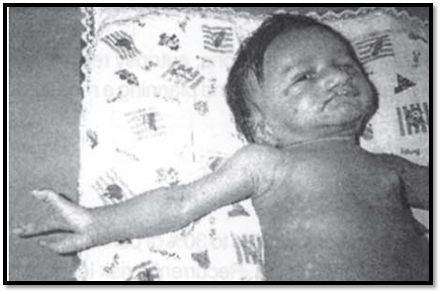

Malformations are primary structural defects that occur during development of a tissue or an organ. A malformation develops from an abnormality during the course of development. Examples of malformations are cleft lip and palate, congenital heart disease, pyloric stenosis and meningomyelocele. Most of the single gene malformations are polygenic/multifactorial, in origin with a low risk of recurrence. Surgical treatment is recommended for correction. Multiple malformation syndromes comprise of defects in two or more systems and are associated with mental retardation (Fig. 2). The recurrence risk depends on the cause, whether it is chromosomal, teratogenic or a single gene defect or unknown.

Fig. 2: Multiple congenital anomalies